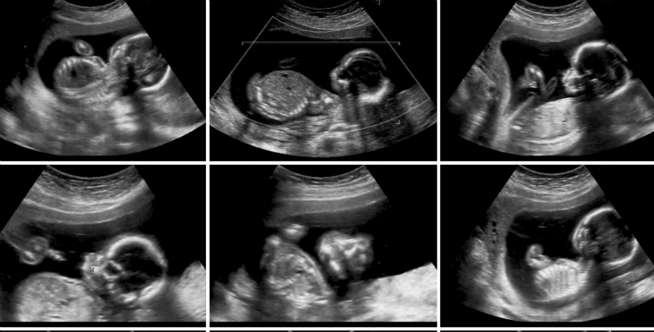

Dream - Klaim seorang ilmuwan asal China yang sudah melakukan rekayasa genetika terhadap seorang bayi dan telah lahir, menghebohkan dunia kedokteran dan genetika. He Jiankui, sang ilmuwan, mengaku dirinya berhasil " menciptakan" manusia pertama dengan rekayasa genetika.

Jiankui mengungkap kalau ia bisa menghilangkan berbagai gen buruk yang tidak diinginkan dari embrio manusia. Dalam sebuah video yang beredar, Jiankui mengatakan kalau dirinya menggunakan alat rekayasa genetika bernama CRISPR-Cas9.

Ia mengklaim telah menghapus sebuah gen pada embrio yang membuat bayi tersebut menjadi resisten dari HIV. Dikutip dari Live Science, Jiankui menjelaskan bahwa dua embrio tersebut telah lahir menjadi bayi kembar sehat yang dinamai Lulu dan Nana.